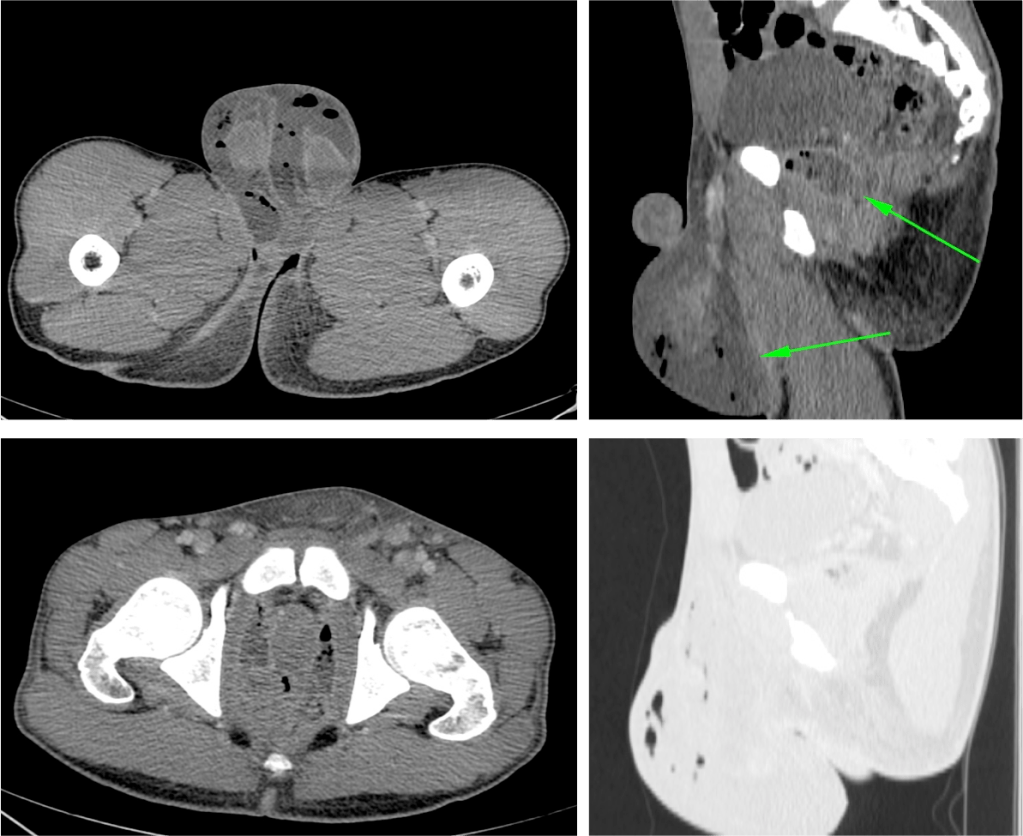

Tomografía Computarizada

Es la técnica que aprota mayor información, por ejemplo nos permite estudiar el retroperitoneo (se han publicado casos de Gangrena de Fournier por perforación de apéndice cecal). Define la causa, muestra el camino por el que se ha extendido el proceso y define las estructuras necrosadas,

- Engrosamiento de fascias e infiltración de partes blandas.

- Presencia de gas.

- Sirve para definir la extensión de proceso previa la cirugía.

- Permite identificar la etiologia del proceso (absceso perianal, fístula, hernias incarceradas, procesos retroperitonales, úlcera de partes blandas…).